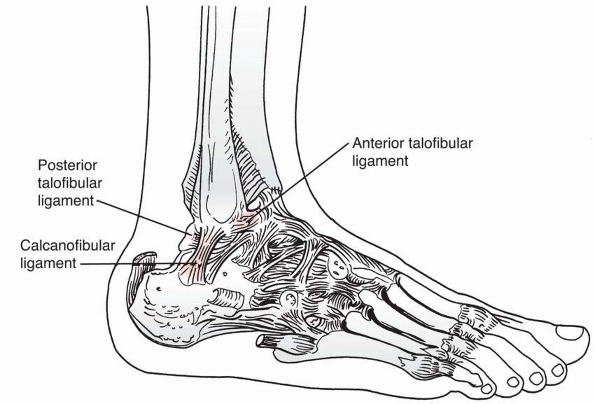

reported, and one of the fractures can be missed if adequate images are

not obtained.81

![]() |

|

FIGURE 26-13 Anteroposterior (A), lateral (B), and oblique (C) views of the ankle demonstrating an apparent small juvenile Tillaux fracture in a 14-year-old girl.